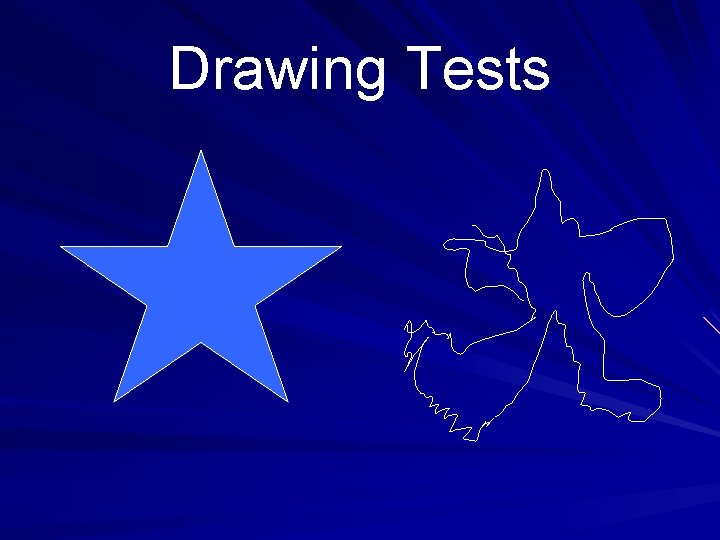

Signs include: Fetor hepaticus Flapping tremor (asterixis) Constructional apraxia (the patient is unable to draw a five-pointed star) The ability to join numbers and letters with a pen within a certain time is prolonged

Drawing Tests